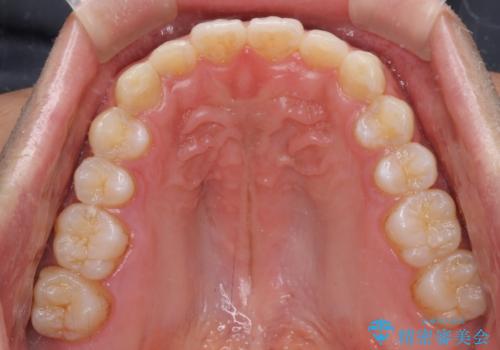

細かい隙間にものがはさまる インビザラインによる矯正治療

- 上下の前歯の隙間を気にして来院された患者様です。

インビザラインを用い、上下歯列のスペースを閉じていくこととしました。

銀行にお勤めのため、突然の転勤により通院が大変な状況となりましたが、インビザラインであれば2-3ヶ月に1度を目安に来院いただき、無事に治療を終えることができました。